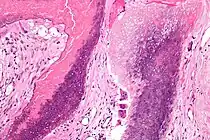

Histopathology of pilomatricoma, high magnification, H&E stain, showing the characteristic components of basaloid cells and ghost cells. | |

The characteristic components of a pilomatricoma include a stroma of fibrovascular connective tissue surrounding irregularly shaped, lobulated islands containing basaloid cells (being darkly stained, round or elongated, with indistinct cell borders and minimal cytoplasm, with nuclei being round to ovoid, deeply basophilic and generally prominent nucleoli), which abruptly or gradually transitions into ghost cells (having abundant, pale, eosinophilic cytoplasm, well defined cell borders and a central clear area, but only faint traces of nuclear material), which in turn may transition into keratinaceous to amorphous necrosis.[11]

The presence of calcifications with foreign-body giant cells is common within the tumors.[12]